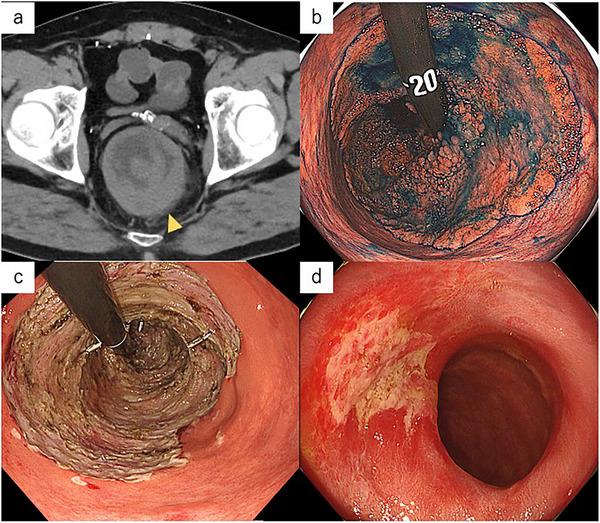

Electrolyte depletion syndrome (EDS), also known as McKittrick-Wheelock syndrome, is a rare but life-threatening condition caused by secretory diarrhea from colorectal villous tumors, often accompanied by severe electrolyte imbalances and renal dysfunction. Large, circumferential tumors have traditionally been managed with surgical resection, frequently requiring stoma formation. Recently, endoscopic submucosal dissection (ESD) has emerged as a minimally invasive alternative, although its feasibility for large rectal tumors remains limited. We report a case of EDS caused by a giant circumferential rectal villous tumor measuring approximately 28 cm, successfully treated with ESD. A 58-year-old man presented with persistent diarrhea, electrolyte disturbances, and acute kidney injury. Imaging and endoscopy revealed a circumferential villous tumor extending from the anal verge to the rectosigmoid colon, diagnosed as a villous adenoma without malignancy on biopsy. After careful discussion between the departments of gastrointestinal surgery and gastroenterology, ESD under general anesthesia was selected to avoid colectomy and stoma creation. En bloc resection of a 280 × 240 mm tumor was achieved without major complications. Prophylactic steroid injection and systemic steroid administration prevented post-ESD stricture. Histopathology revealed adenocarcinoma with minimal submucosal invasion (800 µm), no lymphovascular invasion, and negative resection margins, indicating curative resection. At 6-month follow-up, no recurrence or stricture was observed. This case highlights the potential of ESD as a definitive and less invasive treatment option for EDS caused by large rectal villous tumors when performed with appropriate therapeutic planning and meticulous postoperative care.

电解质耗竭综合征(EDS),也称为麦基特里克 - 惠洛克综合征,是一种罕见但危及生命的疾病,由结直肠绒毛状肿瘤引起的分泌性腹泻所致,常伴有严重的电解质失衡和肾功能障碍。传统上,巨大的环形肿瘤通过手术切除进行治疗,通常需要造口。最近,内镜下黏膜下剥离术(ESD)已成为一种微创替代方法,尽管其对大型直肠肿瘤的可行性仍然有限。我们报告一例由直径约28 cm的巨大环形直肠绒毛状肿瘤引起的EDS病例,通过ESD成功治疗。一名58岁男性出现持续性腹泻、电解质紊乱和急性肾损伤。影像学和内镜检查显示一个从肛门边缘延伸至直肠乙状结肠的环形绒毛状肿瘤,活检诊断为无恶性的绒毛状腺瘤。经过胃肠外科和胃肠病学部门的仔细讨论,选择在全身麻醉下进行ESD以避免结肠切除术和造口。成功整块切除了一个280×240 mm的肿瘤,无重大并发症。预防性类固醇注射和全身类固醇给药预防了ESD后狭窄。组织病理学显示腺癌,黏膜下浸润最小(800 µm),无淋巴管浸润,切缘阴性,表明为根治性切除。在6个月的随访中,未观察到复发或狭窄。该病例突出了ESD作为一种明确且侵入性较小的治疗选择的潜力,用于治疗由大型直肠绒毛状肿瘤引起的EDS,前提是进行适当的治疗规划和精心的术后护理。